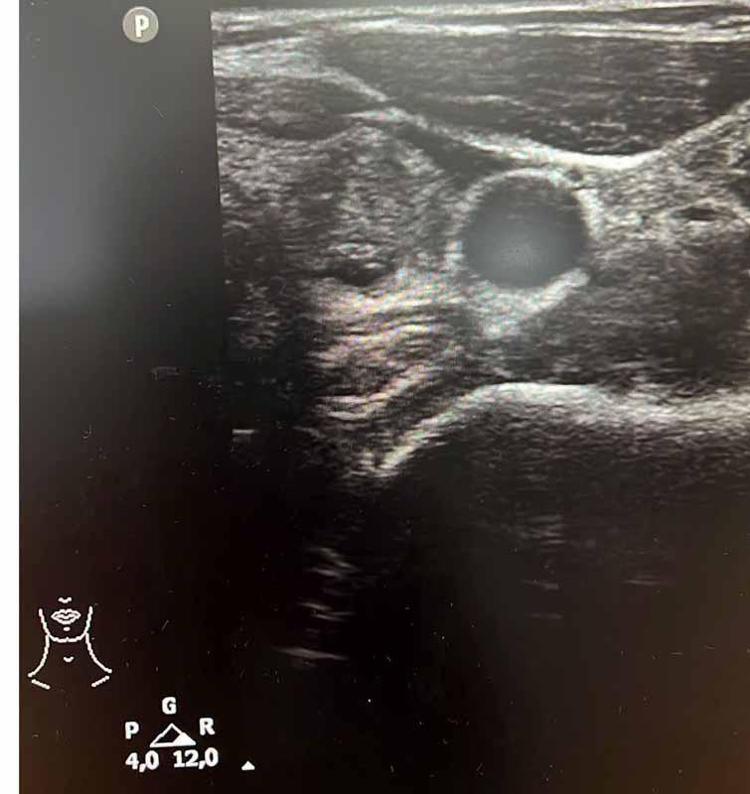

Tiroit nodülü tespitinde farkındalığın artığını ifade eden Dr. Demir, "Nodül tespitindeki farkındalığımız arttı. Tiroit ultrasonu kullanıyor olmamız da bu artışa etken oldu. 'Bası bulgusu' ile dokunarak muayene ettiğimizde; mevcut olan nodüllerin yaklaşık yüzde 20’sini tespit edebiliyoruz. Nodüllerin birçoğunun özelliklerini ve boyutlarını ise tiroit ultrasonu ile tespit ediyoruz. Son dönemlerde vakalarda artış var.

Bazen hiçbir semptomu olmayan hastalarda da tiroit nodülleri tespit ediyoruz. Nodülleri özelliklerine göre değerlendirerek gerekli hastalardan biyopsi alıyoruz. İyi ya kötü huylu nodüle göre tedavi uyguluyoruz. Nodülü belli aralıklarla takip ediyoruz. Tiroit nodüllerinin yüzde 10 ila 20 kadarı kötü huylu olabiliyor. Birçok kanser türü erkek hastalarda fazla görülürken, özellikle tiroit kanseri sıklığı kadın hastalarımızda daha yüksektir. Kadın hastalar daha sık muayeneye geliyor ve farkındalıkları daha yüksek" diye konuştu.